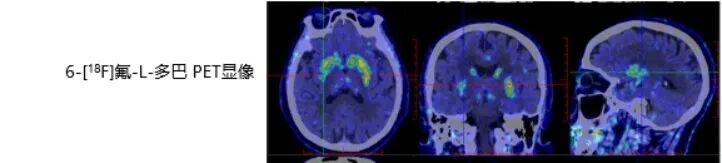

刘阿姨脑多巴代谢显像呈典型PD表现:双侧尾状核及壳核多巴胺能神经末梢分布减低,以右侧壳核后部更显著